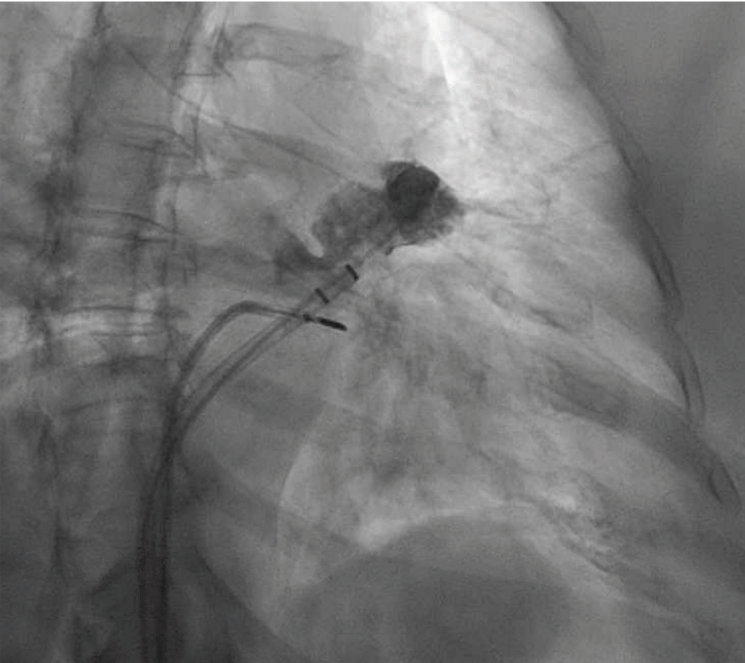

quickly adopted for most cases. The typical workflow for incorporating the 4D ICE catheter involves femoral venous access in the usual manner. To begin a case, the catheter is inserted into the right atrium (RA) and screened for pericardial effusion. Using the V-Plane feature, the LV pericardium can be visualized as well. The catheter is then deflected across the tricuspid valve and into the right ventricular outflow tract. V-Plane through the appendage, in addition to standard 2D imaging, can exclude LAA thrombus (Figure 1). The catheter is withdrawn back to the RA and imaging of the interatrial septum is obtained to help guide transseptal puncture in the usual manner. Once puncture is completed, the septum is flossed with the transseptal sheath. The sheath is then pulled back to the inferior vena cava (IVC). The ICE catheter is then withdrawn to the low RA with direct visualization of the wire as it crosses the septum. Under ultrasound and fluoroscopic guidance, the ICE catheter is pushed across the septum into the mid LA. The delivery sheath is then pushed across the puncture site into the LA. The ICE catheter can be positioned in different locations throughout the LA; however, placement along the mitral annulus frequently allows adequate visualization of the LAA (Figure 2). Multiplanar imaging of the LAA allows for device sizing and selection (Figure 3). Once a device size is selected, the implant is prepped and delivered using multiplanar and fluoroscopic imaging. During sheath manipulation and device delivery, the sonographer can make fine adjustments to the image to maintain adequate visualization so the operator can focus on device delivery. Once an implant is delivered, confirmation of position and occlusion can easily be performed by color flow Doppler and 2D/3D imaging (Figure 4). At the end of the procedure, a quick survey can exclude pericardial effusion.